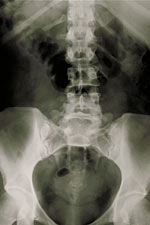

What are X-rays of the spine, neck, or back?

X-rays use energy beams to make pictures of tissues, bones, and organs on film or a computer. Standard X-rays are done for many reasons. These include diagnosing tumors, bone injuries, and other reasons for spine pain.

X-rays pass through body tissues onto special plates similar to camera film. This makes a "negative" type picture. The more solid a structure is, the whiter it looks on film. Instead of film, X-rays are now often made by using computers and digital media.

When X-rays pass through the body, different parts of the body allow different amounts of the X-ray beams to pass through. Images show up with some parts light and other parts dark. How light or dark the areas are depends on the amount of X-rays that pass through the tissues. The soft tissues in the body, such as blood, skin, fat, and muscle, let most of the X-ray pass through. These areas look dark gray on the film. A bone or a tumor is denser than soft tissue. It does not let many X-rays to pass through and looks white on the X-ray. At a break (fracture) in a bone, the X-ray beam passes through the broken area. It's seen as a dark line in the white bone.

X-rays of the spine may be done to look at areas of the spine. These are the cervical, thoracic, lumbar, sacral, and coccygeal sections. Other imaging tests may also be used to diagnose spine, back, or neck problems. These are myelography (myelogram), CT scan, MRI, and bone scans.